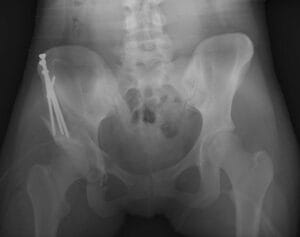

- X-rays: X-rays provide images of bones and help the doctor assess the alignment between the acetabulum and femoral head. They can also reveal signs of arthritis.